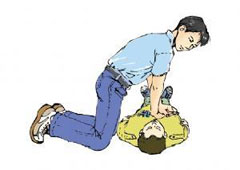

严重颅脑损伤、多发伤、复合伤

疾病介绍:严重颅脑损伤、多发伤、复合伤,多为交通、工矿事故、自然灾害、爆炸、火器伤、坠落、跌倒以及各种锐气、钝器对人体伤害。除正确诊断和及早手术外,加…【详细】